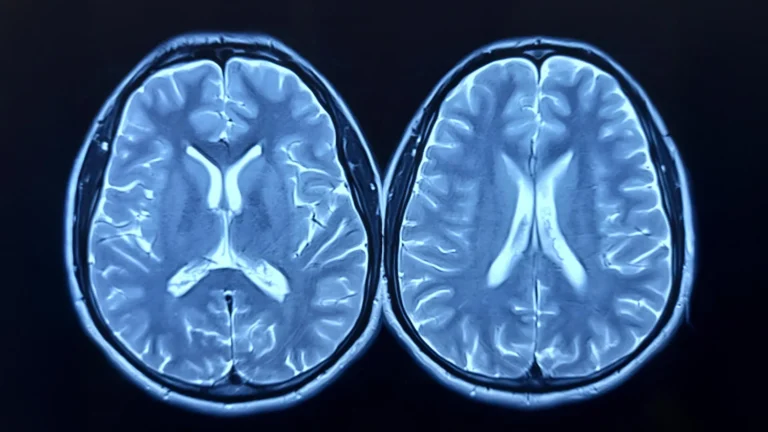

The intricate biochemical pathways within the human brain are fundamental to our cognitive functions, emotional well-being, and...